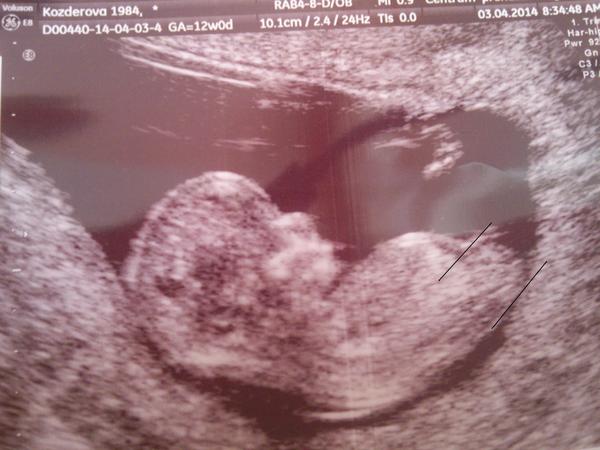

Poznáte na fotce z UTZ, jestli je to kluk nebo holka?

Asi takhle - tohle pozná leda hodně zkušený gynekolog (u nás to ve 13.tt poznali a je to holčička znovu dvakrát potvrzená....a snad už jí ten pinďa fakt nenaroste 🙂 ) Ve 13tt pohlaví ještě vypadá u obojího pohlaví stejně, nejde poznat "zespodu", jak uvádí @matous24, to až později, pouze ze sklonu toho pohlavního výběžku - holčičky ho mají spíš dopředu rovnoběžně s páteří, chlapečkům spíš "trčí" vzhůru. To, co trčí nahoru, je podle mě ha, je to moc velké na genitální výběžek. ALE - vidím tam i před "nohou" takový náznak výběžku (nebo si myslím, že je to ono) a zde podle toho, že je spíš rovnoběžný než směrem nahoru, tak bych tipovala spíš holčičku (měli jsme též). Ale jinak je to fakt padesát na padesát prostě 🙂

@ninive211 no praaaave 😀 podle té kustky bych řekla taky že holčička 😀 jinak jasnacka že cekam cekam a taky čekám dvojcatka a to druhé nejde vidět vůbec tak říkám že to bude chlapeček ale tady ta fotecka má tu kustecku tak horizontálně s páteří tak si říkám že ta je holčička 😀

Ve 13. tt nic nepoznáš, kord z téhle fotky... To chce ještě počkat a mít fotku ze spodu... 🙂